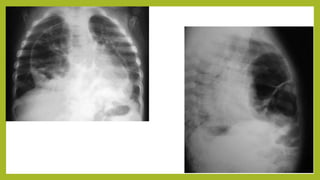

• Se realiza Rayos X de Tórax (vista lateral y posteroanterior) donde se evidencia

invasión del estómago al hemitorax izquierdo a través del defecto

diafragmático, compatible con la entidad clínica del paciente.

• Además se confirma un área de atelectasia a nivel del tercio medio del campo

pulmonar izquierdo